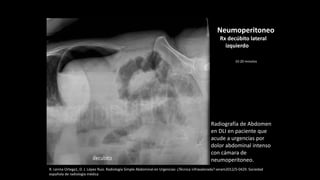

Radiografía de Abdomen

en DLI en paciente que

acude a urgencias por

dolor abdominal intenso

con cámara de

neumoperitoneo.

Neumoperitoneo

Rx decúbito lateral

izquierdo

10-20 minutos